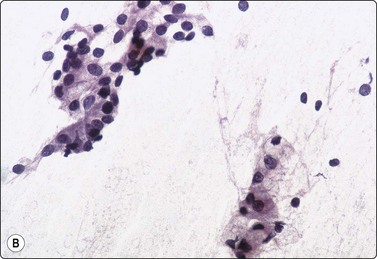

image image

Fig. 4.9 Nasopharyngeal carcinoma (undifferentiated, lymphoepithelial type, WHO type III)

Loose clusters of undifferentiated epithelial cells with vesicular nuclei, prominent nucleoli and pale fragile cytoplasm. Background of lymphocytes. (A, MGG, HP; B, H&E, HP).

Nasopharyngeal carcinoma (NPC) is a clinicopathologic entity different from other squamous cell carcinomata of the head and neck. It is distinguished by its particular histology, geographic distribution, relationship to Epstein-Barr virus, and the absence of an alcohol or tobacco etiological relationship. A proportion of NPCs show squamous differentiation and the cytological pattern of non-keratinizing squamous cell carcinoma (squamous cell carcinoma/WHO type II) (Fig. 4.8). Keratinized cells (WHO type I) are uncommonly found. The majority of NPC are poorly differentiated or undifferentiated. Cells from undifferentiated NPC (UCNT, WHO type III) form loose clusters with no specific microarchitectural pattern, and are usually mixed with lymphoid cells. In the ‘lymphoepitheliomatous’ type (Schmincke-Regaud) the cells tend to be less cohesive, resembling Hodgkin’s disease or large cell non-Hodgkin lymphoma. However, in NPC, the malignant cells are still clustered and have more abundant pale cytoplasm contrasting with the lymphoid cells in the background (Fig. 4.9). Plasma cells are frequently found among the lymphoid cells. Immunostaining for cytokeratin and a pan-lymphocyte marker is helpful. Epstein-Barr virus-associated nuclear antigen is demonstrable by anticomplement immunofluorescence in undifferentiated tumors. Other patterns of growth may occur and may cause diagnostic problems; for example, spindle cell forms may be difficult to recognize as carcinoma.